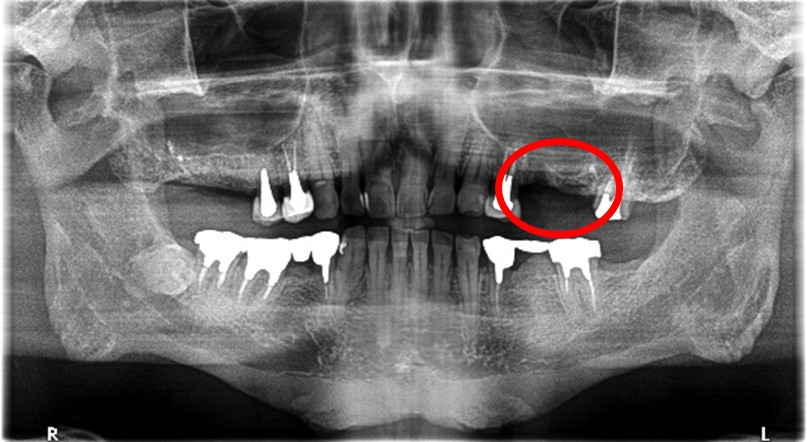

レントゲンで詳しく診てみると、歯根が真っ二つに割れていることがわかりました。臭いは、割れているために炎症を引き起こし、そこからの膿が原因でした。保存することができず抜歯しました。抜歯後、インプラントを埋入しました。

抜歯後、ブリッジ、部分入れ歯の選択肢もありましたが、2013年に右下にインプラント治療をし、インプラントの良さを十分に理解しておられましたので、今回も1本歯を失ったところにインプラント治療を希望されました。歯根破折が原因で抜歯になった方ですので、もしブリッジにしていたら再度歯根の破折を引き起こし、さらに歯を失う可能性が、高い方でした。インプラントは、それ自身が単体で植立し、単独で咬合力を負担します。ブリッジや部分入れ歯のように他の歯に歯がない部分の負担を負わせることがないので、他の歯を守ります。インプラントにして正解だと考えます。今回もX-Guideを使った埋入で、安心安全に行うことができました。

歯根が真っ二つに割れていました

抜いた歯